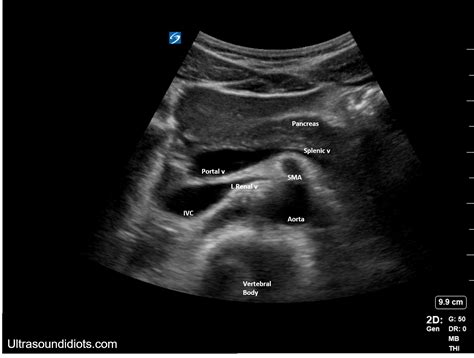

An ultrasound of abdomen is used to evaluate a wide range of conditions affecting the abdominal organs. Some of the most common uses include:

• Liver and Gallbladder: Assessing the size, shape, and structure of the liver and gallbladder. Detecting conditions such as gallstones, liver tumors, and inflammation.

• Pancreas: Evaluating the pancreas for inflammation, tumors, or cysts.

• Spleen: Checking the spleen for enlargement, cysts, or tumors.

• Kidneys: Examining the kidneys for stones, tumors, cysts, or other abnormalities.

• Bladder: Assessing the bladder for stones, tumors, or other issues.

• Abdominal Aorta: Checking for aneurysms or other abnormalities in the abdominal aorta.

Interpreting the Results of an Ultrasound of Abdomen

The images obtained from an ultrasound of abdomen are reviewed by a radiologist, who provides a detailed report to the referring physician. The results can help diagnose various conditions, including: